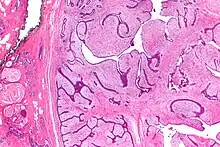

| Micrograph of a phyllodes tumor (right of image) with the characteristic long clefts and myxoid cellular stroma. Normal breast and fibrocystic change are also seen (left of image). H&E stain. |

Phyllodes tumors (from Greek: phullon), are a rare type of biphasic fibroepithelial mass that form from the periductal stromal and epithelial cells of the breast.[1] They account for less than 1% of all breast neoplasms.[2] They were previously termed cystosarcoma phyllodes, coined by Johannes Müller in 1838, before being renamed to phyllodes tumor by the World Health Organization in 2003.[3] Phullon, which means 'leaf' in Greek, describes the unique papillary projections characteristic of phyllodes tumors on histology.[1] Diagnosis is made via a core-needle biopsy and treatment is typically surgical resection with wide margins (>1 cm), due to their propensity to recur.[4]